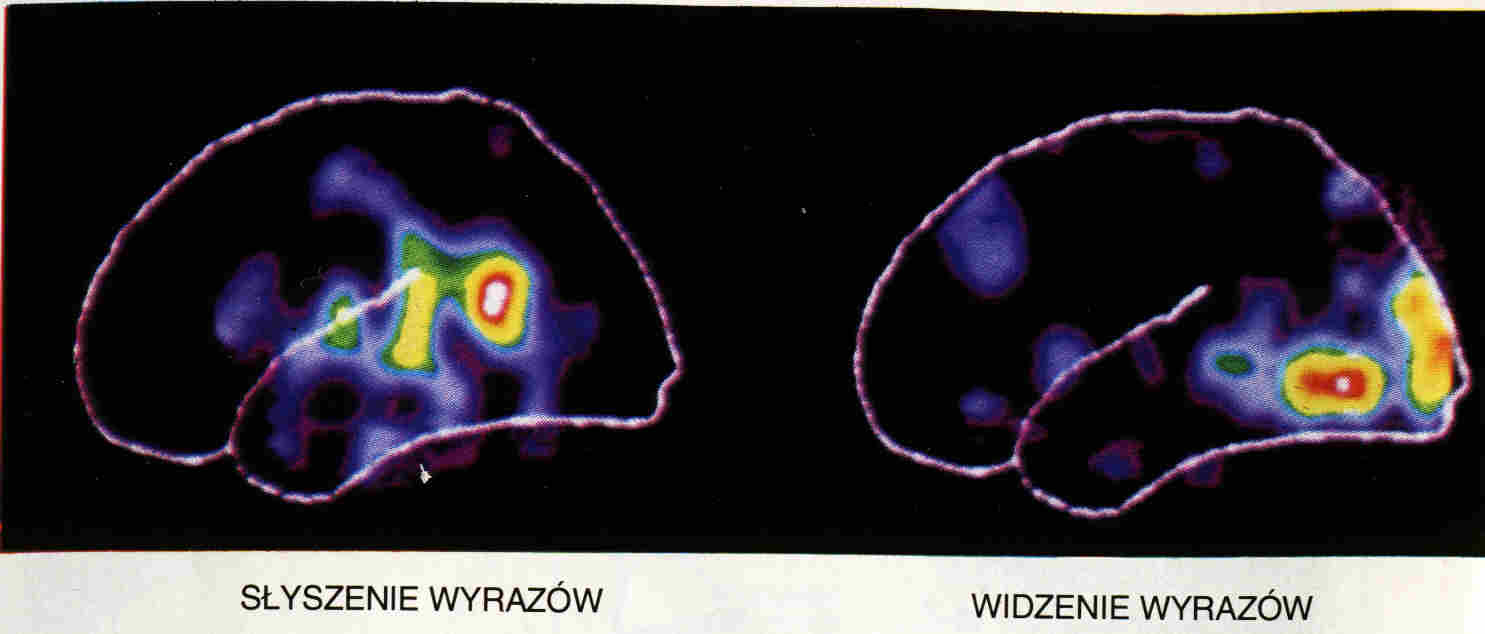

Analizując percepcję musimy się zastanowić, czy nasza fenomenologia pasuje do fizycznych podstaw powstawania wrażeń, a więc rozchodzenia się aktywacji neuronalnej w mózgach.

Na co reagują pola recepcyjne kory zajmującej się analizą danych zmysłowych? Nawet najprostsze bodźce - z punktu widzenia naszych wyobrażę - wywołują złożone reakcje mózgu. Co jest dla mózgu proste? Czy są takie bodźce, które wywołują powtarzalną, zlokalizowaną reakcję?

Neurofenomenologia powinna lepiej powiązać fizyczną aktywność obszarów w mózgu z subiektywnie postrzeganymi wrażeniami.

Pierwotna kora słuchowa zajmuje pola kory skroniowej 41/42 Brodmanna, zakręt skroniowy przedni poprzeczny (zakręt Heschla), schowany w bruździe bocznej, pod stykiem płata czołowego i ciemieniowego, na płacie skroniowym.